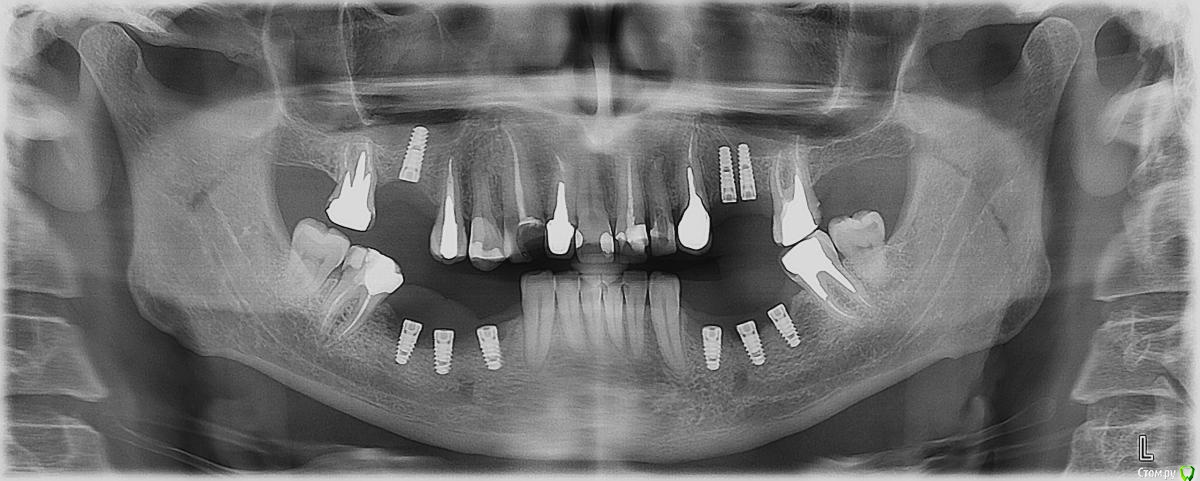

rezo47 Опубликовано 28 июля, 2015 Поделиться Опубликовано 28 июля, 2015 Добрый день коллеги! Обратился пациент на этап протезирования, имплантаты поставлены год назад в нашей клинике. Врач пациенту сказал появиться через 6 мес. но пациент не пришел, сам врач этот уже не работает. Мукозит появился около 3 мес. назад, боли нет. Отправил на ОПГ, кости нет, причем слева тоже невсе ок, но об этом позже. А пока демаю что с этим всем делать. План мой таков:- иссечь в пределах здоровых тканей;- удалить имплантаты 46;45;- контроль через 2 мес. Выслушаю любые предложения Ссылка на комментарий

Доктор Добрых Дел Опубликовано 28 июля, 2015 Поделиться Опубликовано 28 июля, 2015 (изменено) Если вести речь об удалении имплантатов, то тогда всех трёх, так как не вижу особой разницы по состоянию костной ткани между, например, 44 и 45. К тому же позиции имплантатов далеки от идеальных. На счёт иссечения согласен, на счёт удаления - может быть есть смысл сначала сделать КТ .На ОТПГ вроде язычная стенка прослеживается, может быть удастся сохранить Изменено 28 июля, 2015 пользователем Доктор Добрых Дел Ссылка на комментарий

kriokov Опубликовано 28 июля, 2015 Поделиться Опубликовано 28 июля, 2015 Справа 3 убирать надо. Как рану потом вести подумать надо. Может раскрыться линейно,выкрутить болты, убрать только грануляции с кости, потом иссечь мягкие до живых и под тампоном вести? Пац повторную имплант планирует? Представляет что за дефект будет? Язычная останется только у 44 Ссылка на комментарий

АнтонТЛТ Опубликовано 28 июля, 2015 Поделиться Опубликовано 28 июля, 2015 Слева тоже бы убрал. Справа мягкие ткани бы нее иссекал, само всё должно восстановиться после удаления имплантатов Ссылка на комментарий